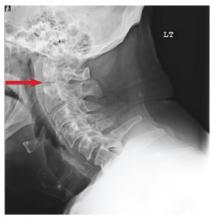

A 72-year-old nursing home resident is sent for evaluation of decreased level of consciousness, nausea, vomiting, and increasing confusion. He denies any recent injury or trauma. His medical history is significant for diabetes, stroke, dementia, atrial fibrillation, and hypertension. The patient denies any head or neck pain. His vital signs are stable. Overall, aside from reports of occasional confusion, his physical examination is benign. He moves all of his extremities well and appears to have no deficits, including no neck or back tenderness. In reviewing his lab work, you see his sodium concentration is 126 mEq/L. CT of the head shows only chronic changes. Cervical spine radiographs are also obtained; the lateral view is shown. What is your impression?

The radiograph demonstrates a lucency at the base of the odontoid (C2). In addition, there is a slight posterior subluxation of C1 on C2.

Although these findings were deemed likely to be chronic and old in nature, for completeness, an MRI of the cervical spine was obtained. It did, in fact, confirm the findings to be old.